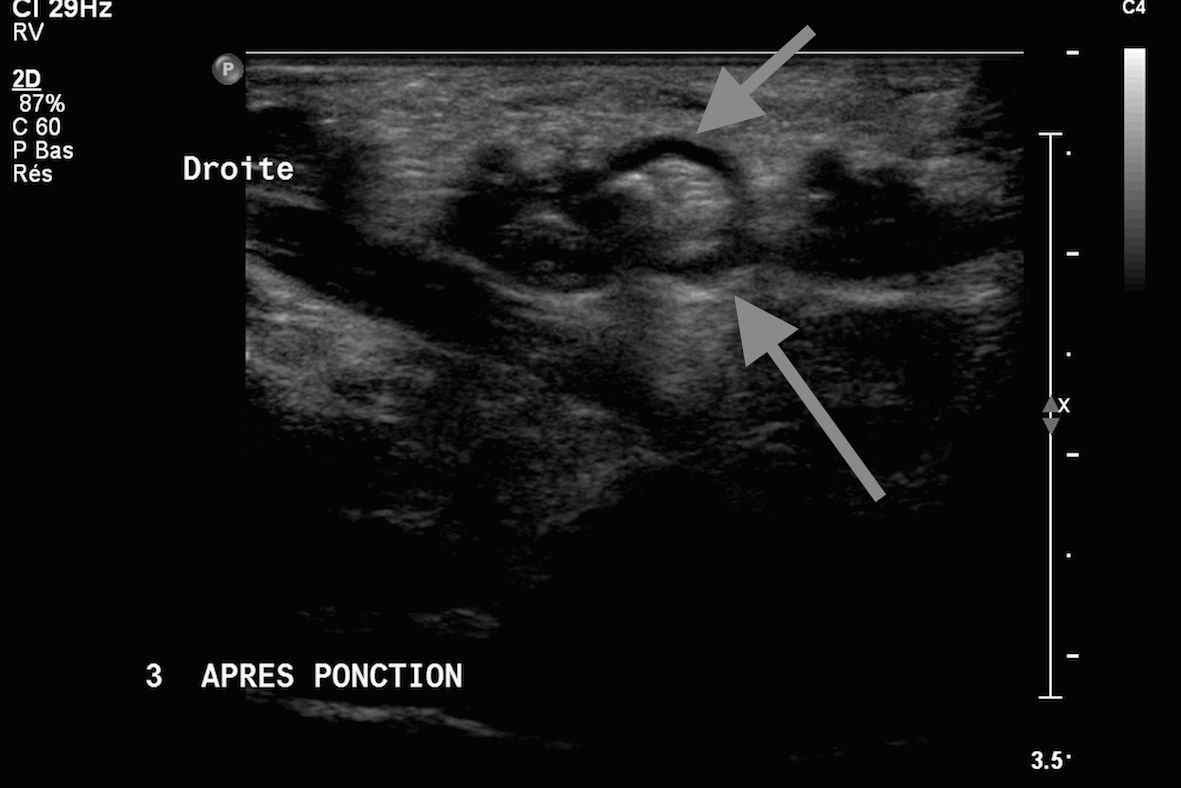

Infiltration d'une bursite calcanéenne sous contrôle échographique image 1

Images 2, 3 et 4 aiguille en place dans la zone hypodense (burste) sous deux incidences orthogonales